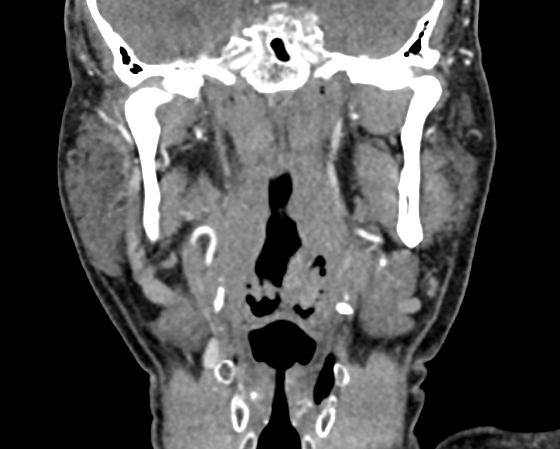

Одним из методов диагностики заболеваний носоглоточной области является мультиспиральная компьютерная томография. Методика предусматривает использование рентгеновского излучения. Благодаря различной способности тканей поглощать рентгеновские лучи и последующей цифровой обработке полученных данных, удается получить изображения исследуемой зоны в мельчайших подробностях. Рентгеновские лучи лучше всего поглощаются плотными тканями, такими как костная ткань, поэтому кости хорошо видны на снимках КТ.

При необходимости улучшения визуализации мягкотканных структур и особенно при подозрении на опухолевый процесс, применяется внутривенное болюсное контрастирование. Йодсодержащее контрастное вещество вводится пациенту в вену, после чего оно попадает в кровеносную систему и с током крови разносится по организму. Патологические очаги в большей степени накапливают контраст, что на снимках придает им детальность и яркие очертания на фоне окружающих здоровых тканей.

Инновационные цифровые приложения томографов позволяют получить снимки высокого качества и детализации, а также создать трехмерные реконструкции анатомической зоны исследования, что дает возможность рассмотреть пространственное расположение органов и патологических образований. КТ носоглотки с контрастом назначают при подозрении на рост новообразований, в случае хронического воспаления, при врожденных аномалиях строения носа и прилегающих к нему придаточных пазух.